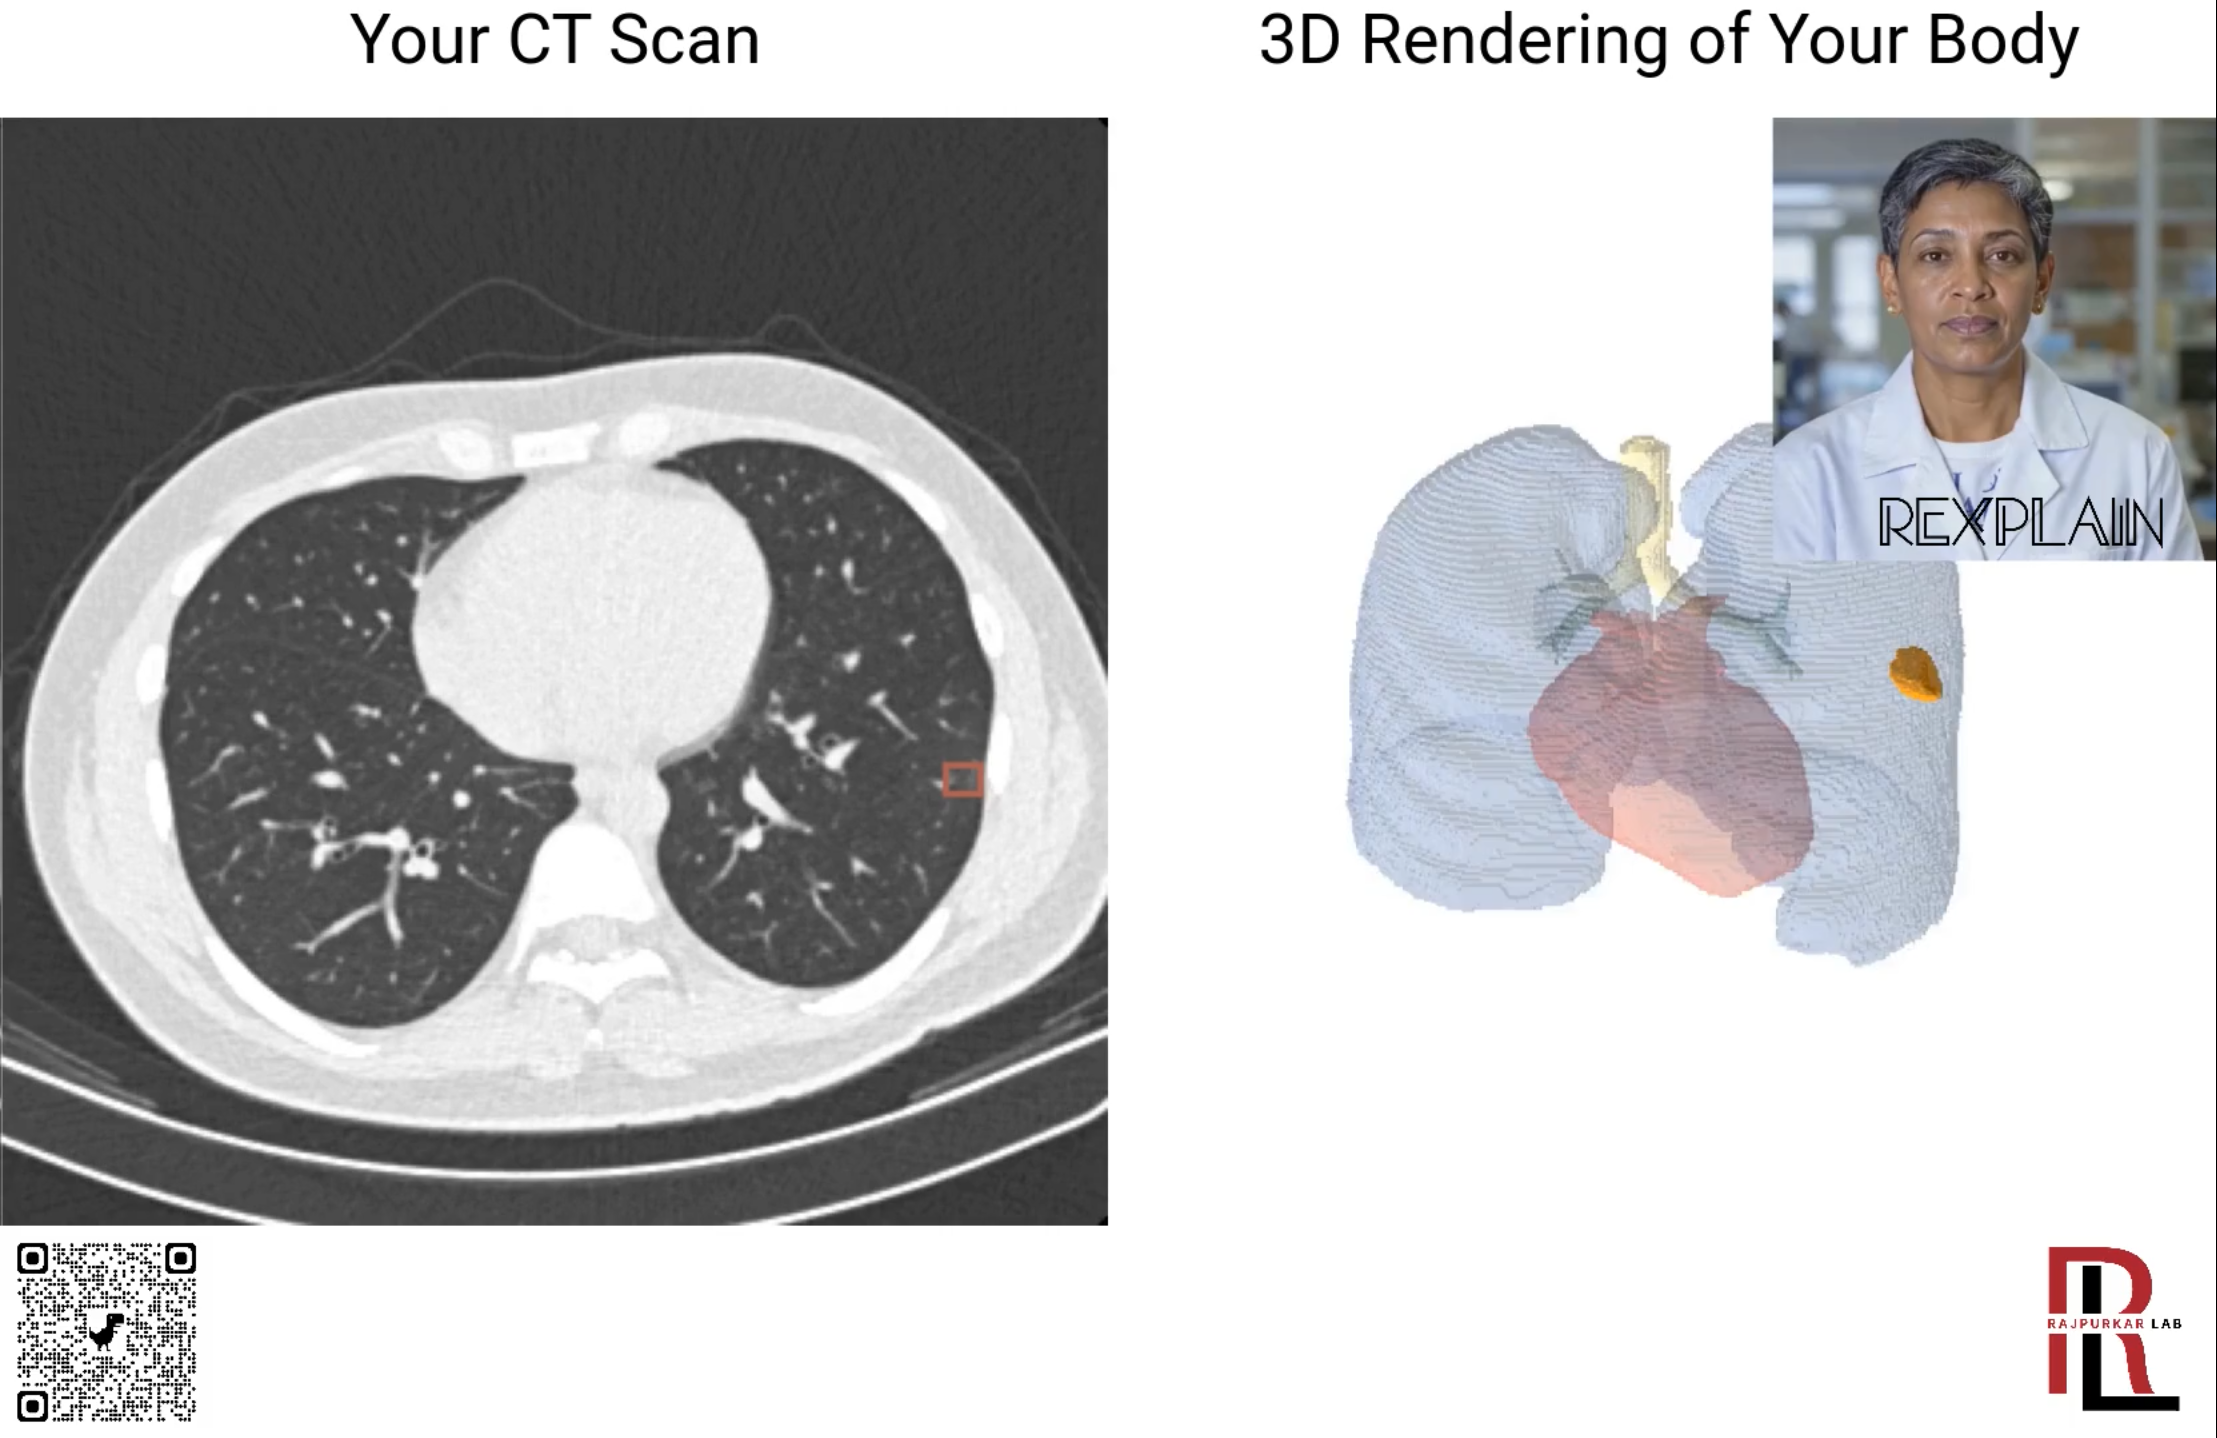

ReXplain

Best Paper

ReXplain: Translating Radiology into Patient-Friendly Video Reports

Luyang Luo, Jenanan Vairavamurthy, Xiaoman Zhang, Abhinav Kumar, Ramon R. Ter-Oganesyan, Stuart T. Schroff, Dan Shilo, Rydhwana Hossain, Mike Moritz, and Pranav Rajpurkar

AAAI AIMedHeath, 2025